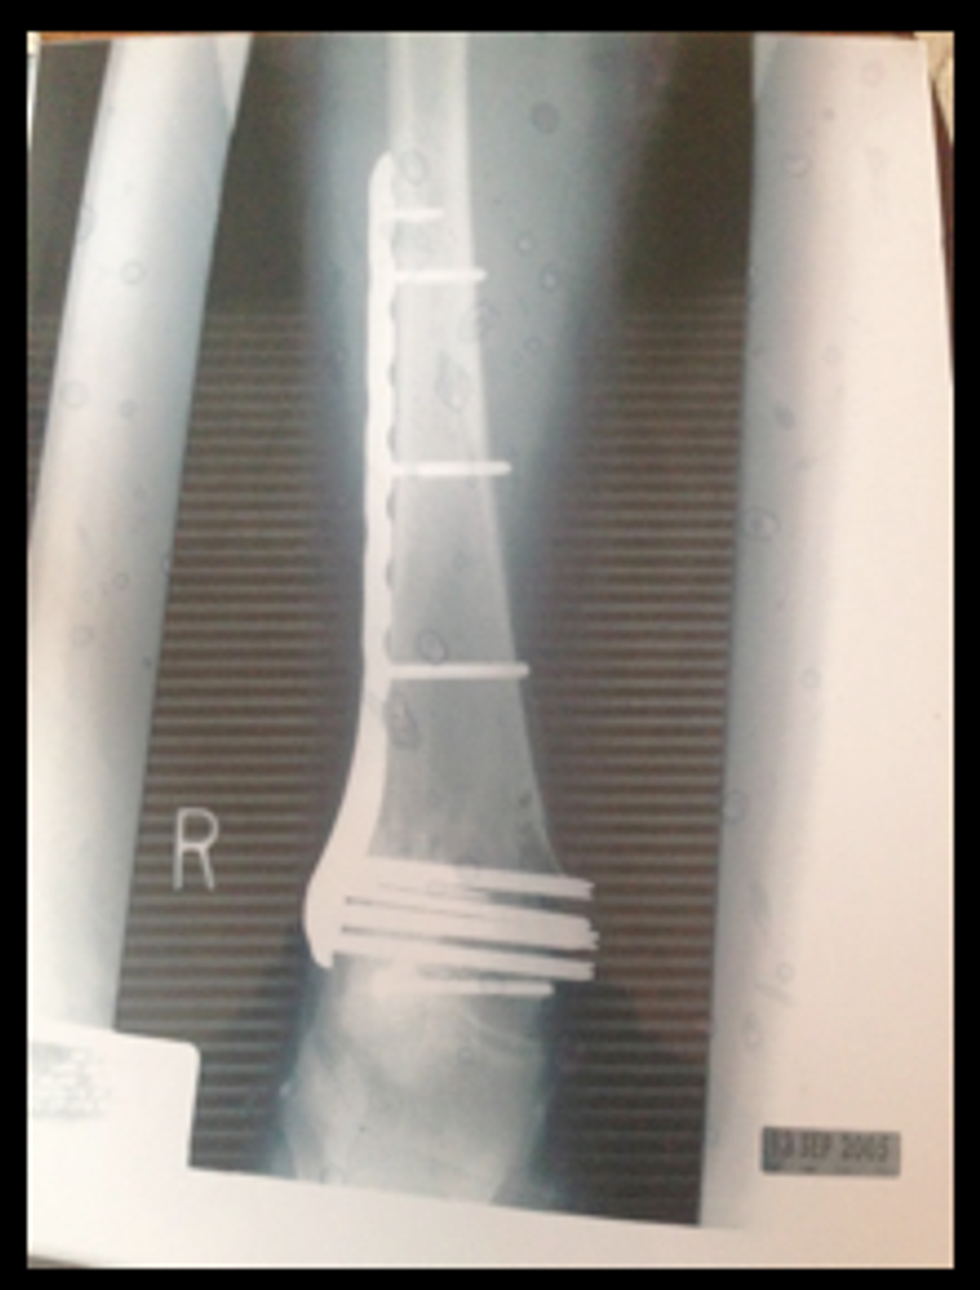

In the hospital, Jill’s medical record read her injuries: two broken feet, a shattered femur, a fractured pelvis, seven broken ribs, a punctured lung, a collapsed lung, a broken nose, and internal bleeding. Her chances of survival at this time were sadly limited.

Because of the impact and angle of the car, her right knee and foot were completely shattered. This caused her to have an external fixator (metal rods, almost like a cage, going through her leg to keep it together) in her leg to hold it all together, on top of having a breathing tube, and tubes in her chest.

Jill spent a total of 96 days in the hospital, has had over 27 surgeries and counting, including a full knee replacement, spent eight months wheelchair bound, missed a year of college, and racked up about a half a million dollars in medical bills.

This accident also resulted in Jill to lose her gall bladder, as she was not eating and was weighing in at about 90 pounds, infusion of her feet, and resulted in her having a long metal plate and screws in her leg and feet. Finally able to come home after a little over three months, she was not the same person she was when she left for ice cream months ago.